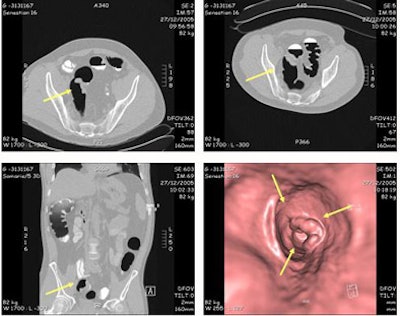

![]() |

| Residual fluid covered less than 20% of the colonic surface, and with prone and supine scanning, did not impair radiologists' ability to interpret data. Images courtesy of Dr. Didier Bielen. |

Residual stool was present in varying amounts in most patients, and stool tagging was homogeneous in just two patients, Bielen said. Even so, the inhomogeneously tagged stool was relatively easy to distinguish from lesions by its texture, and as it changed position between supine and prone scanning.